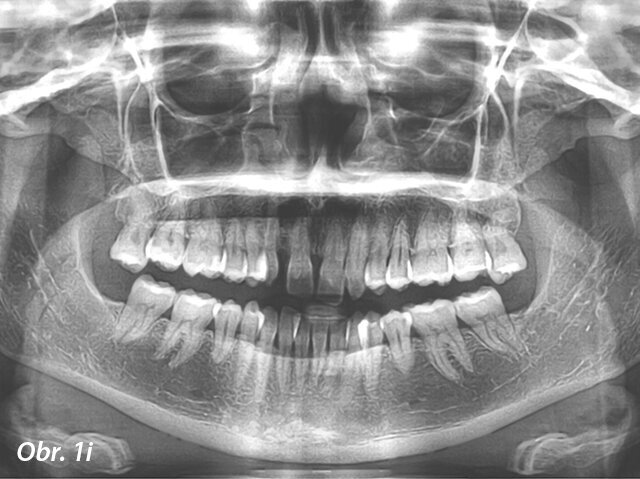

Diagnóza a léčebný plán

Pacientkou byla 30letá žena s konkávním profilem daným hypoplazií horní čelisti s krátkým horním rtem, prominencí dolního rtu, tupým nasolabiá­lním úhlem a skeletální III. třídou s maxilární retrognacií a mandibulární progenií. Co se týče dentálního nálezu, byla u pacientky diagnostikována III. třída s výrazným stěsnáním, obrácený skus, posun střední čáry o 1 mm, nevýrazná Speeova křivka a ageneze horních laterálních řezáků potvrzená na panoramatickém rentgenovém snímku (obr. 1a–j; tab. 1).